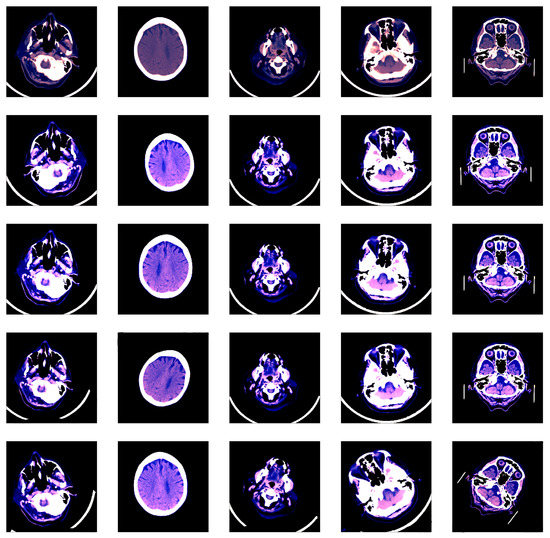

3.1. Data Preprocessing and Augmentation